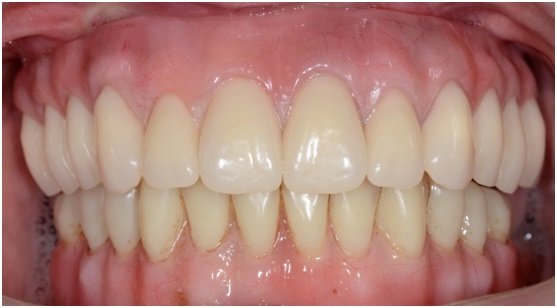

Sua queixa principal era falta de estabilidade de sua prótese total superior, relatou que perdeu os dentes com menos de trinta anos de idade, ou seja, este paciente usa prótese total a mais de trinta anos.